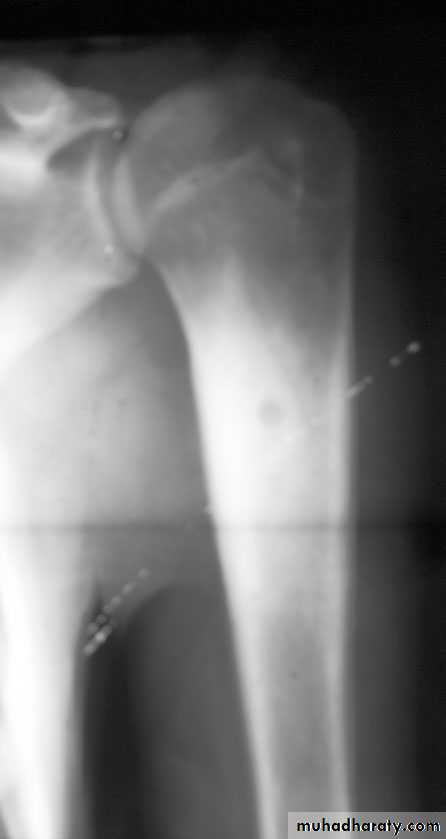

Primary malignant bone tumoursBone : osteosarcoma

Preoperative : (neoadjuvant) 8-12 wAfter tumour resection : check tumour necrosis